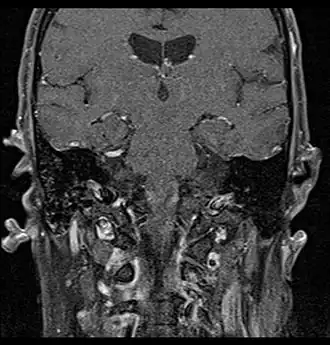

Coronal MRI showing right parotid adenoid cystic carcinoma with perineural spread of tumor: The tumor originates in the right parotid gland and spreads along the trigeminal nerve via the auricuotemporal branch extending intracranially through the foramen ovale at the skull base towards Meckel's cave. -

Coronal MRI showing right parotid adenoid cystic carcinoma with perineural spread of tumor along the facial nerve extending to the stylomastoid foramen -